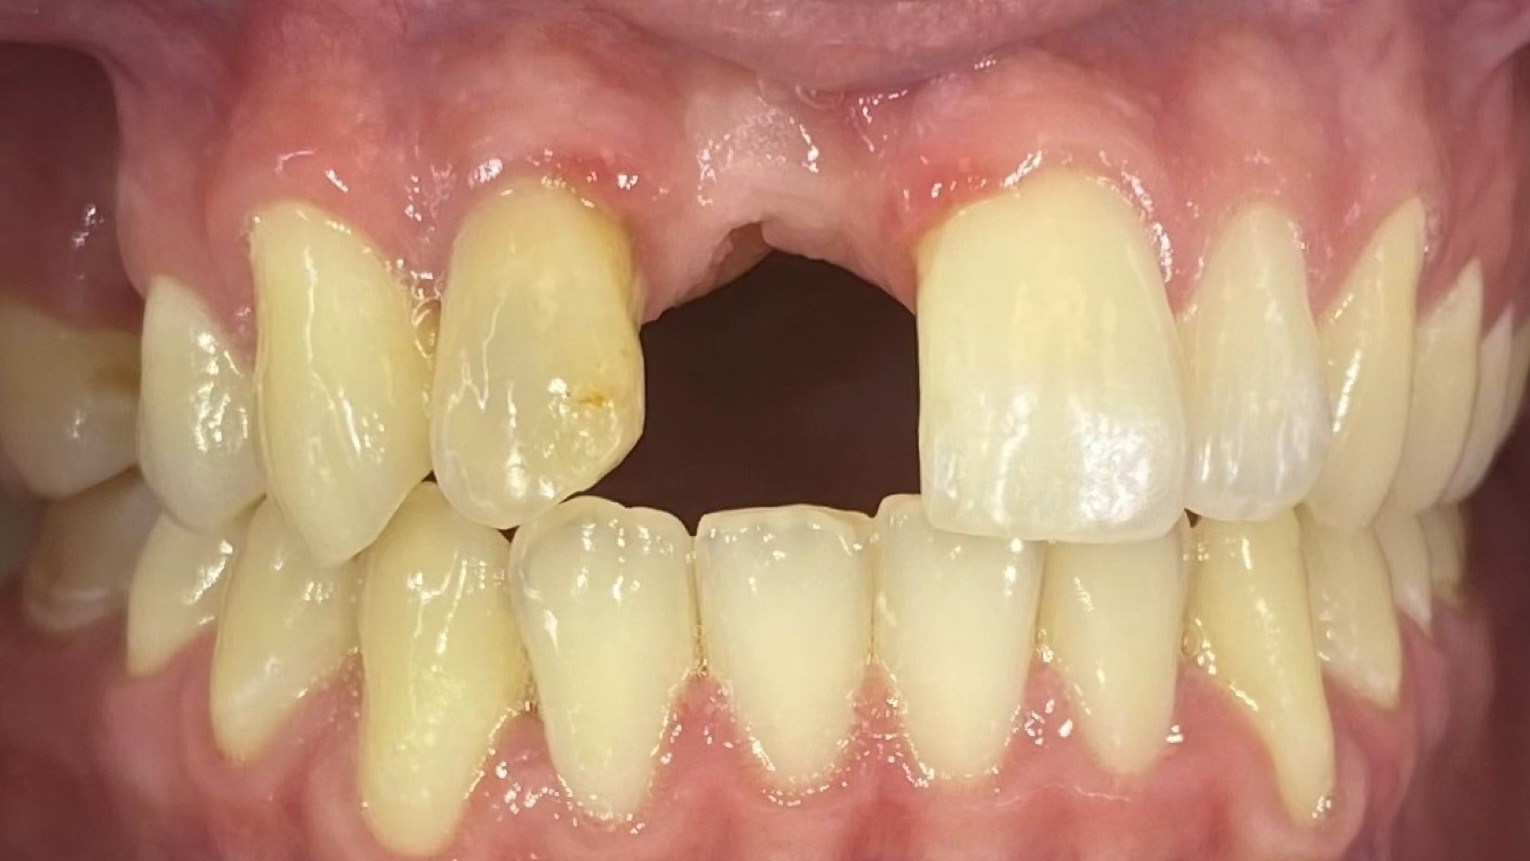

The poster provided a clear and structured overview of the pre-, intra-, and postoperative stages of ceramic implant placement, illustrating:

the dynamics of soft- and hard-tissue healing,

and the long-term functional and aesthetic outcomes achievable with ceramic implants.